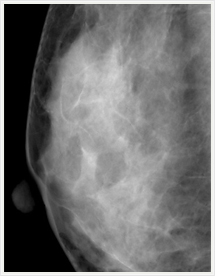

画像紹介

画像は左右を比較するように表示され、気になるところは、拡大して見ることができます。